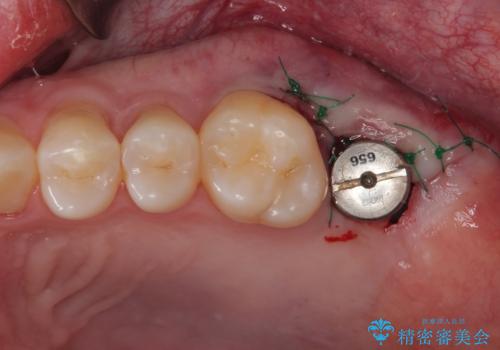

- 他院で虫歯治療の途中の歯を治療したいとのことで来院された患者様です。来院時特に症状もなく、根管治療途中の状態でした。レントゲン上でも大きい病変を認めました。治療方針として再度根管治療を行うか、抜歯をしてインプラントにする二つの方法をご提案しました。

咬み合わせが強く根管治療後の歯の破折のリスクや治療期間の観点からインプラント治療を行っていくこととなりました。

根尖病巣も大きかったため先に抜歯を行い、1ヶ月後にインプラントを埋入しました。